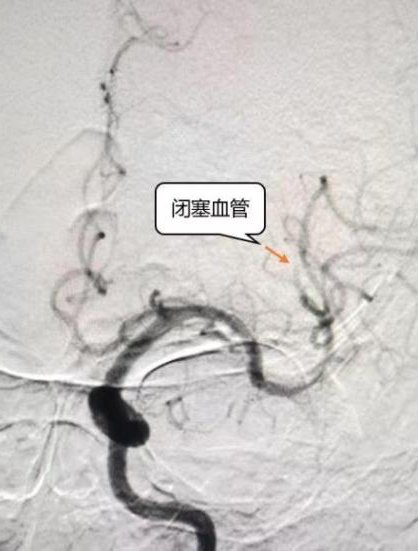

通常情况下,这类手术需要在全麻下进行,考虑到张先生已经85岁,全麻可能对心肺功能造成损伤,赵彦新主任介入手术团队立即召集麻醉科、介入科同事共同商讨,决定在局麻下实施手术,最大程度减少并发症,保证病人安全。脑血管造影中发现张先生左侧大脑中动脉远端分支存在闭塞,赵主任团队通过血管内碎栓抽吸配合溶栓药物治疗,张先生的血管闭塞很快得到了开通,恢复了血流。经过专业、及时的静脉溶栓联合血管内介入治疗,术后第一天张先生就恢复了意识,瘫痪肢体也可自主活动,这一切对于张先生一家都感觉不可思议。